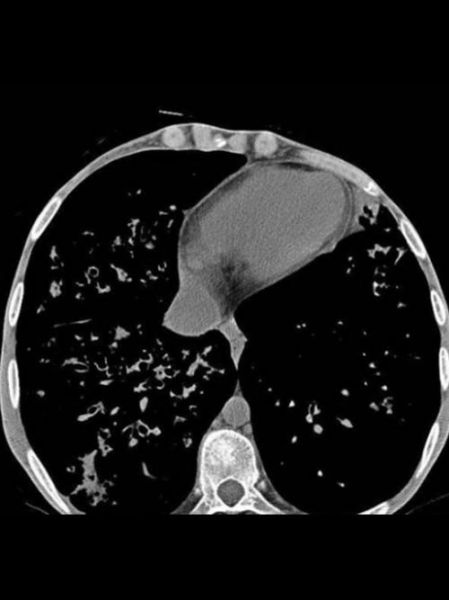

(图片来源网络,侵删)